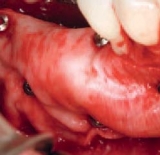

Titan-Nägel